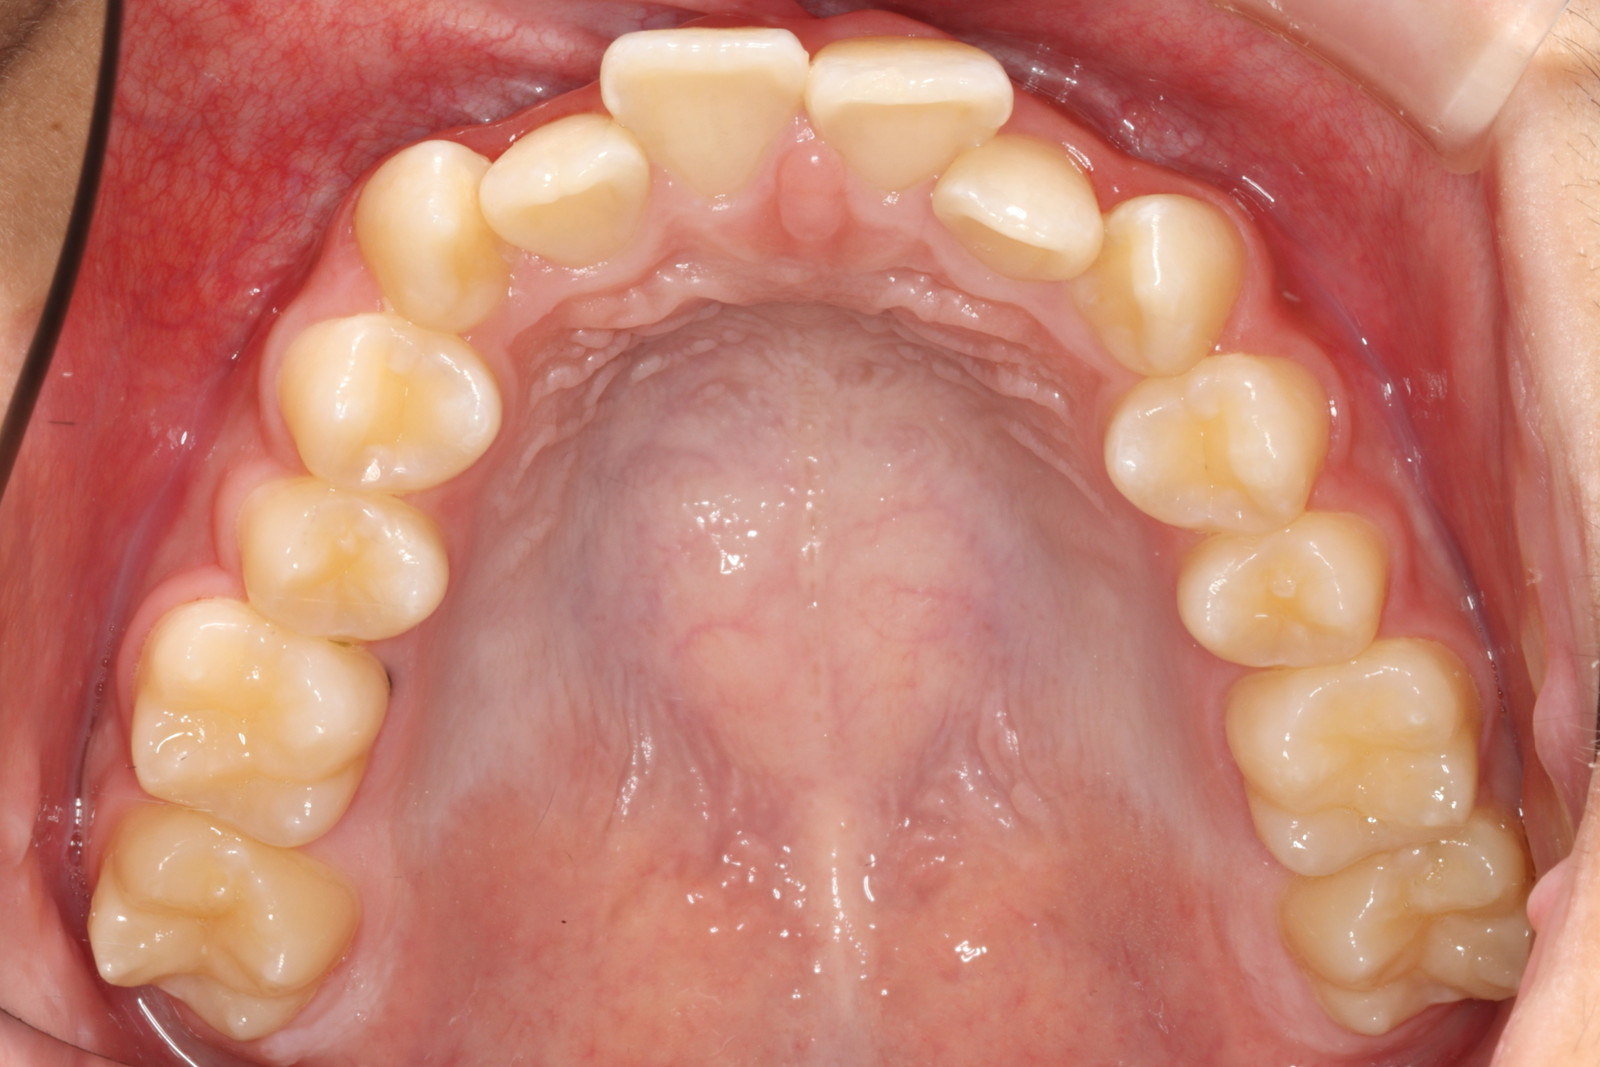

問診を行い、お口の悩みや希望を確認します。レントゲン撮影や口腔内写真の撮影など、必要に応じた精密検査を行います。